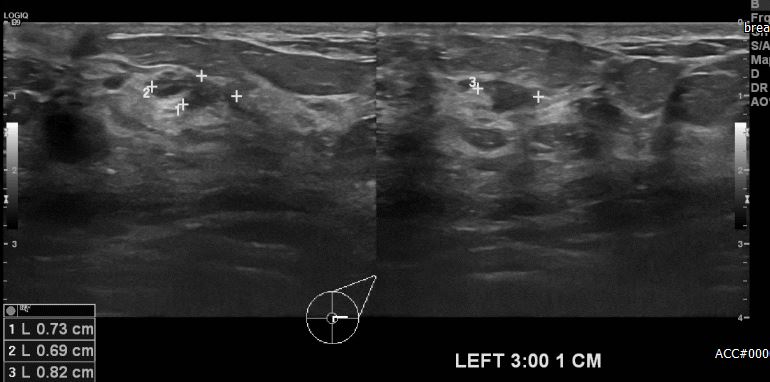

상기환자 건강검진상 이상소견으로 내원하신 40대 여성분으로 본원 초음파상

좌측유방 3시 방향에서 1cm 떨어진 거리에 의심스러운 멍울 조직검삼 시행하여

촤측 침윤성 유관암 진단되었습니다.